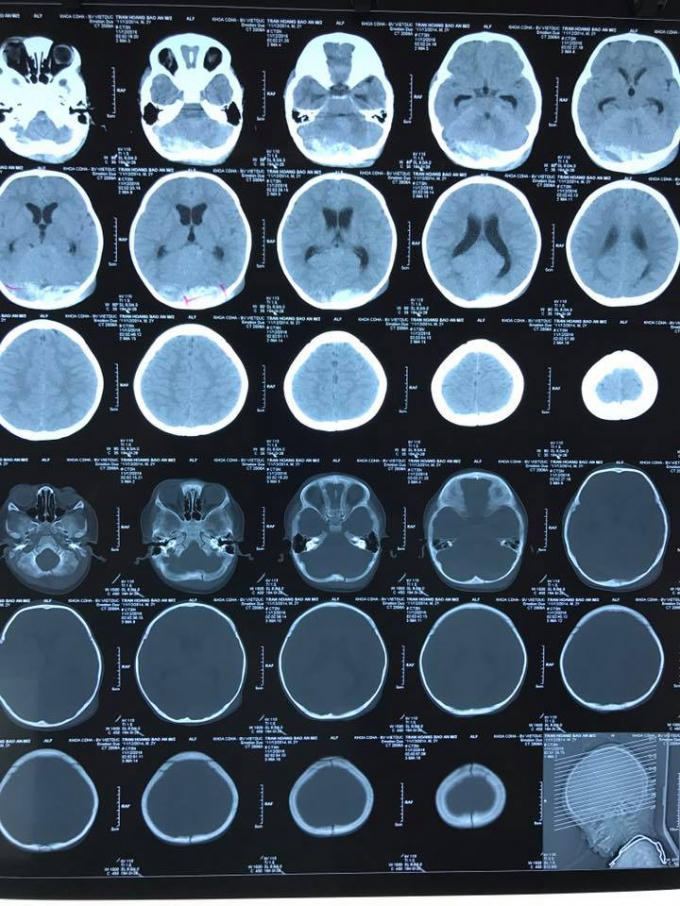

Theo các bác sĩ, bệnh nhi nhập viện trong tình trạng hôn mê, bóp bóng qua nội khí quản, đồng tử đều 1.5mm, huyết động tạm ổn định. Hình ảnh chụp CT- scan sọ não cho thấy bệnh nhi có máu tụ ngoài màng cứng chẩm hai bên.